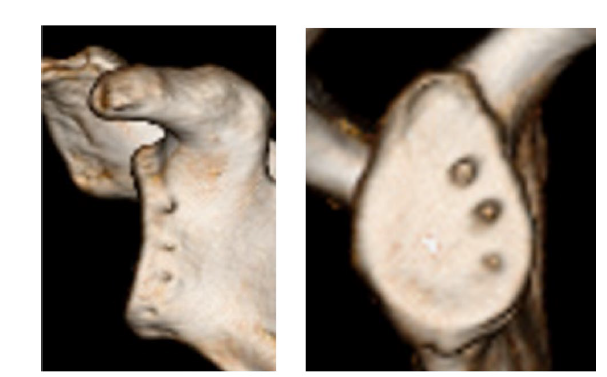

独自の知見:手術後に「骨が再生する(リモデル)」

本治療の最大の特徴は、単に「止める」だけでなく、術後の「骨の質の変化」までを科学的に追い続けている点にあります。

多くの術式では、手術後に関節窩(肩の骨)が吸収されて減少してしまうことが課題でした。しかし、DAFF法を施行した症例をCTで精密に追跡した結果、「術後1年で新しい骨が形成され、骨の幅が回復する」という画期的な事実を確認しました(日本肩関節学会にて発表)。

強固な固定によって適切な物理的ストレスが骨に加わることで、身体本来の再生能力を引き出す。これが、私たちが目指す「一生涯、再脱臼させない肩」の根拠となっています。